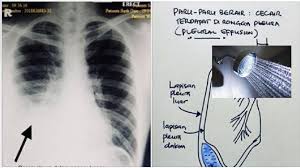

Penyebabnya beragam, seperti infeksi virus dan bakteri. Tanda khasnya ada pada intensitas, keparahan, dan gejala tambahannya. Posted by ummuziyad on august 9, 2017 in no comments. Masalah jantung (cardiogenic pulmonary edema). Mulai dari batuk, sesak napas, nyeri, perubahan suara, lelah, bengkak, dan masih banyak lagi. Jenis bendalir tersebut adalah bedasarkan punca penyakit iaitu sama ada jenis exudate (bendalir yang mempunyai kandungan protein tinggi) atau tansudate (berair). Keadaan ini berlaku kerana berlakunya kecederaan pada permukaan. Tbc.asma.sembuh 100% dengan ( minyak herbal jum 1000 ) sudah tersedia di tokopedia.bukalapak.shopee.salam sehat kita semua. Gangguan kesehatan ini terbilang umum di indonesia, dan termasuk jenis penyakit yang tidak menular. Infeksi akut pada paru bincang sehati. Betul ke mandi malam penyebab paru paru berair. Atau sistem pernapasan pada manusia dan juga terdiri dari bagian pulmo dextra atau paru paru kanan dan pulmo sinistra paru paru kiri. Punca paru paru bocor @ pneumothorax.